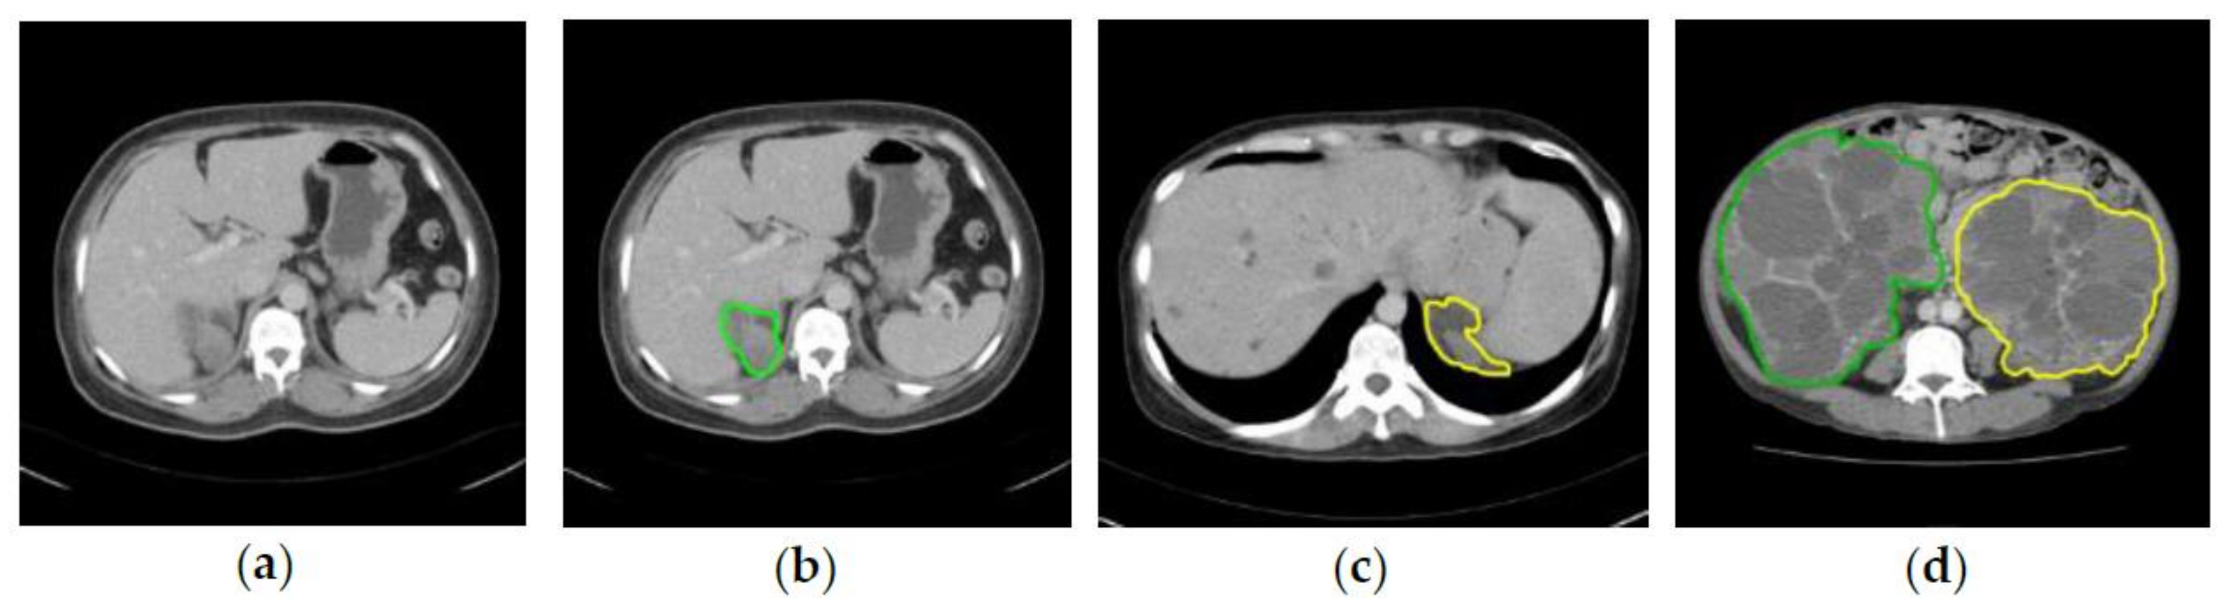

2.2. Ground Truth Annotation

2.3.3. Bounding Box Labeling